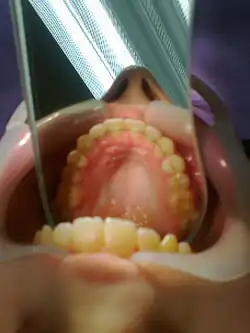

После завершения исправления прикуса, ретейнер фиксируется специальным композитным материалом на лингвальную (внутреннюю) поверхность передних шести зубов и носится там до полного завершения ретенционного периода и стабилизации зубов в новом положении. После выравнивания зубов брекет-системой, ретейнер устанавливается врачом-ортодонтом и, как правило, остаётся у пациента пожизненно, в противном случае зубы могут снова расстроиться. Ретейнеры вызывают незначительный дискомфорт в первые дни после установки, со временем пациент к ним привыкает и перестаёт замечать.